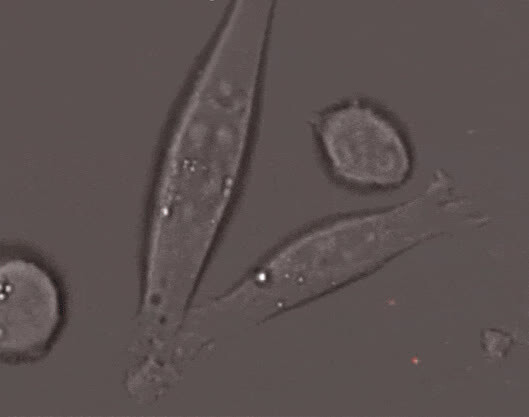

细胞毒性T细胞(也被称为“杀手T细胞”)正在识别受病毒感染、癌变之类的“不正常细胞”,导致细胞死亡。整个动图实际用时约为75分钟。

7、在显微镜下“实地”拍摄一场免疫细胞的战争场面,免疫系统vs癌细胞(看的小编热血沸腾)